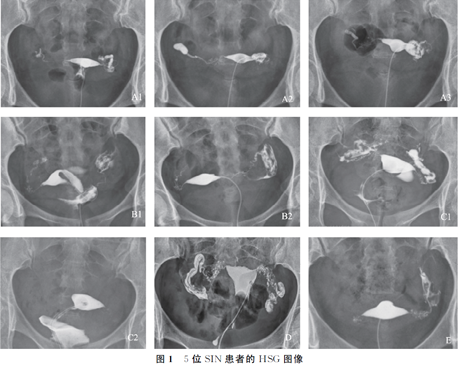

峡部结节性输卵管炎主要通过子宫输卵管造影诊断,早中期表现为输卵管峡部周围多个造影剂聚集的小囊状憩室, 憩室与输卵管主管腔侧壁相通, 憩室直径大小多在0.1-2mm,丛集在长约2厘米输卵管峡部周围,相邻的输卵管间质部有时会累及。此期为SIN的典型表现期。晚期表现为双侧(或单侧)输卵管阻塞或积水。 SIN是一种进展性病变,其HSG表现典型,特征直观,临床上比较容易掌握,进行诊断时操作性好。HSG是诊断SIN最准确最简单可靠的方法。

列举5例不同检查者的部分HSG图像,其中A患者33岁,继发性不孕,行腹腔镜下输卵管近端结扎术后采用试管婴儿助孕分娩一健康女婴。腹腔镜手术时从两侧输卵管各取一段做病理组织检查证实为SIN,共进行3次HSG检查,检查结果见图A1、A2、A3:首次HSG检查为2012年9月6日,表现为双侧输卵管峡部周围多个造影剂聚集的小囊状憩室,双侧输卵管通而不畅,为SIN 的典型早期表现(图A1);2013年5月19日行HSG复查示:右侧输卵管积水,左侧输卵管通而不畅(图A2);2015年5月14日再次复查HSG示:右侧输卵管壶腹部阻塞,左侧输卵管轻度积水(图A3)。B患者24岁,继发性不孕,2015年4月27日行HSG检查示:双侧输卵管峡部周围多个造影剂聚集的小囊状憩室,双侧输卵管通而不畅(图B1);2016年5月8日复查HSG示:右侧侧输卵管峡部远端阻塞,左侧输卵管通而不畅(图B2)。C患者26岁,继发性不孕,HSG示典型早期SIN表现:双侧输卵管峡部周围多个造影剂聚集的小囊状憩室(图C1),10个月后HSG复查显示双侧输卵管间质部阻塞(图C2)。D患者,29岁,继发性不孕,HSG 示典型早期SIN表现:双侧输卵管峡部周围多个造影剂聚集的小囊状憩室,双侧输卵管通而不畅(图D)。E患者,22岁,继发性不孕,既往双侧输卵管各有1次输卵管妊娠史;HSG示:双侧输卵管峡部周围多个造影剂聚集的小囊状憩室,以左侧为著,右侧输卵管峡部远端阻塞(图E)。